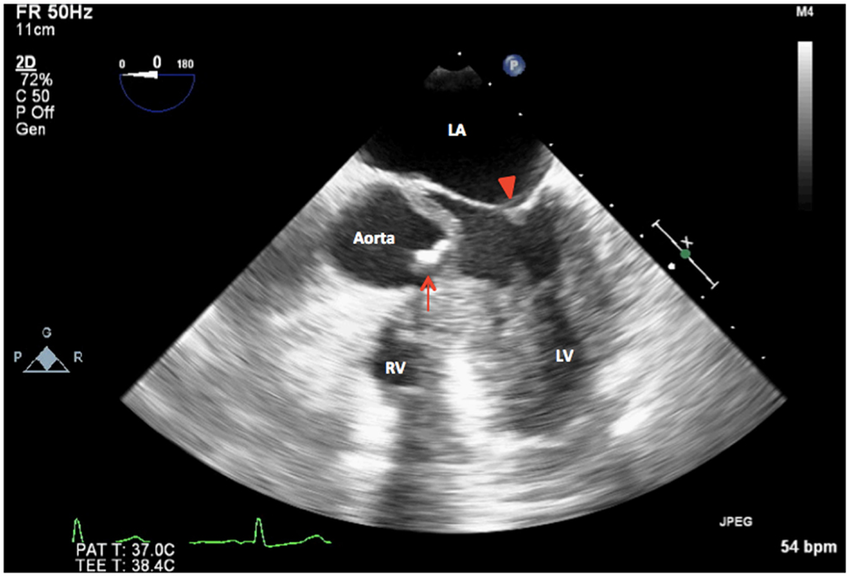

A

Mid esophageal AV long axis view

120- 140 degree (same as Lv long axis)